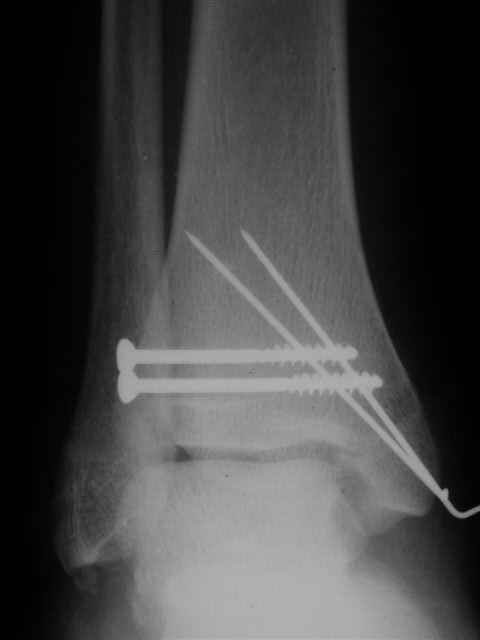

Уважаемый Иван,

Я предупреждал, что ничего сверхъестественного. Каюсь, что одна из спиц прошла несколько дальше, чем нужно было, но главное - перелом стабилизирован и больной работает суставом в полном объёме, несмотря на представленную раннее травму коленного сустава.

Всего вам Доброго,

Евгений И Чекашкин